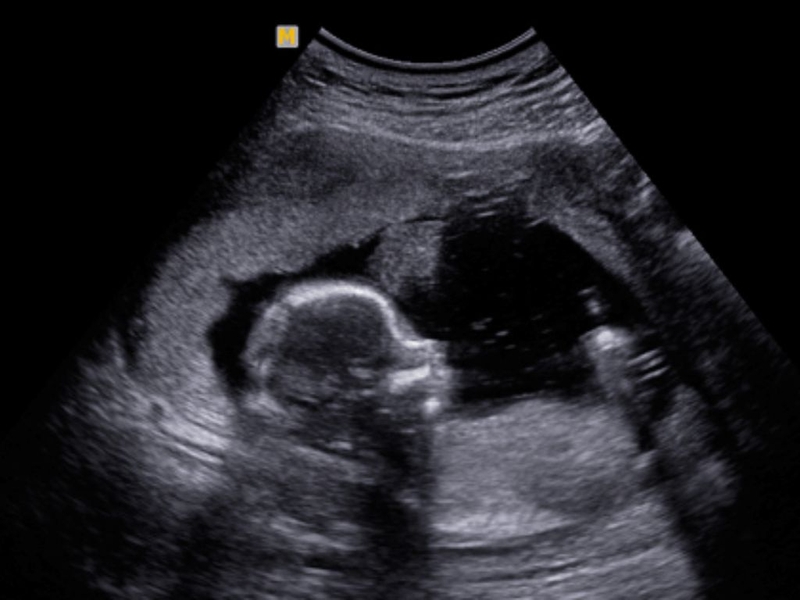

Để biết chính xác thai 16 tuần phát triển như thế nào các bác sĩ sẽ tiến hành siêu âm hình ảnh. Sau đây là những chỉ số thai nhi cho thấy thai 16 tuần khỏe mạnh và phát triển bình thường: